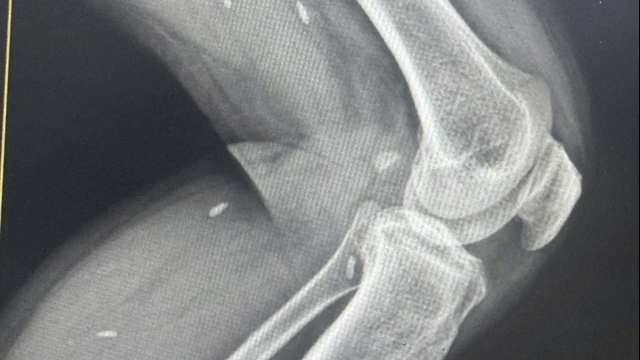

Ông P có tiền sử xơ gan rượu, nhập viện trong tình trạng viêm mô mềm nặng, hoại tử vùng cẳng và bàn tay. Bệnh nhân đã được điều trị kháng sinh tích cực chống viêm, cắt lọc vùng hoại tử và chờ ghép da.